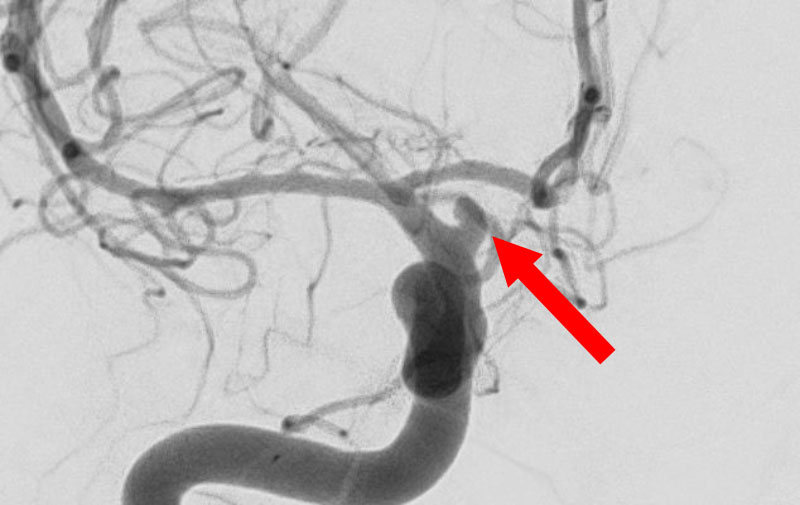

'25年10月

くも膜下出血

右内頚動脈脳動脈瘤破裂

40代

救急外来

No.1592 手術前